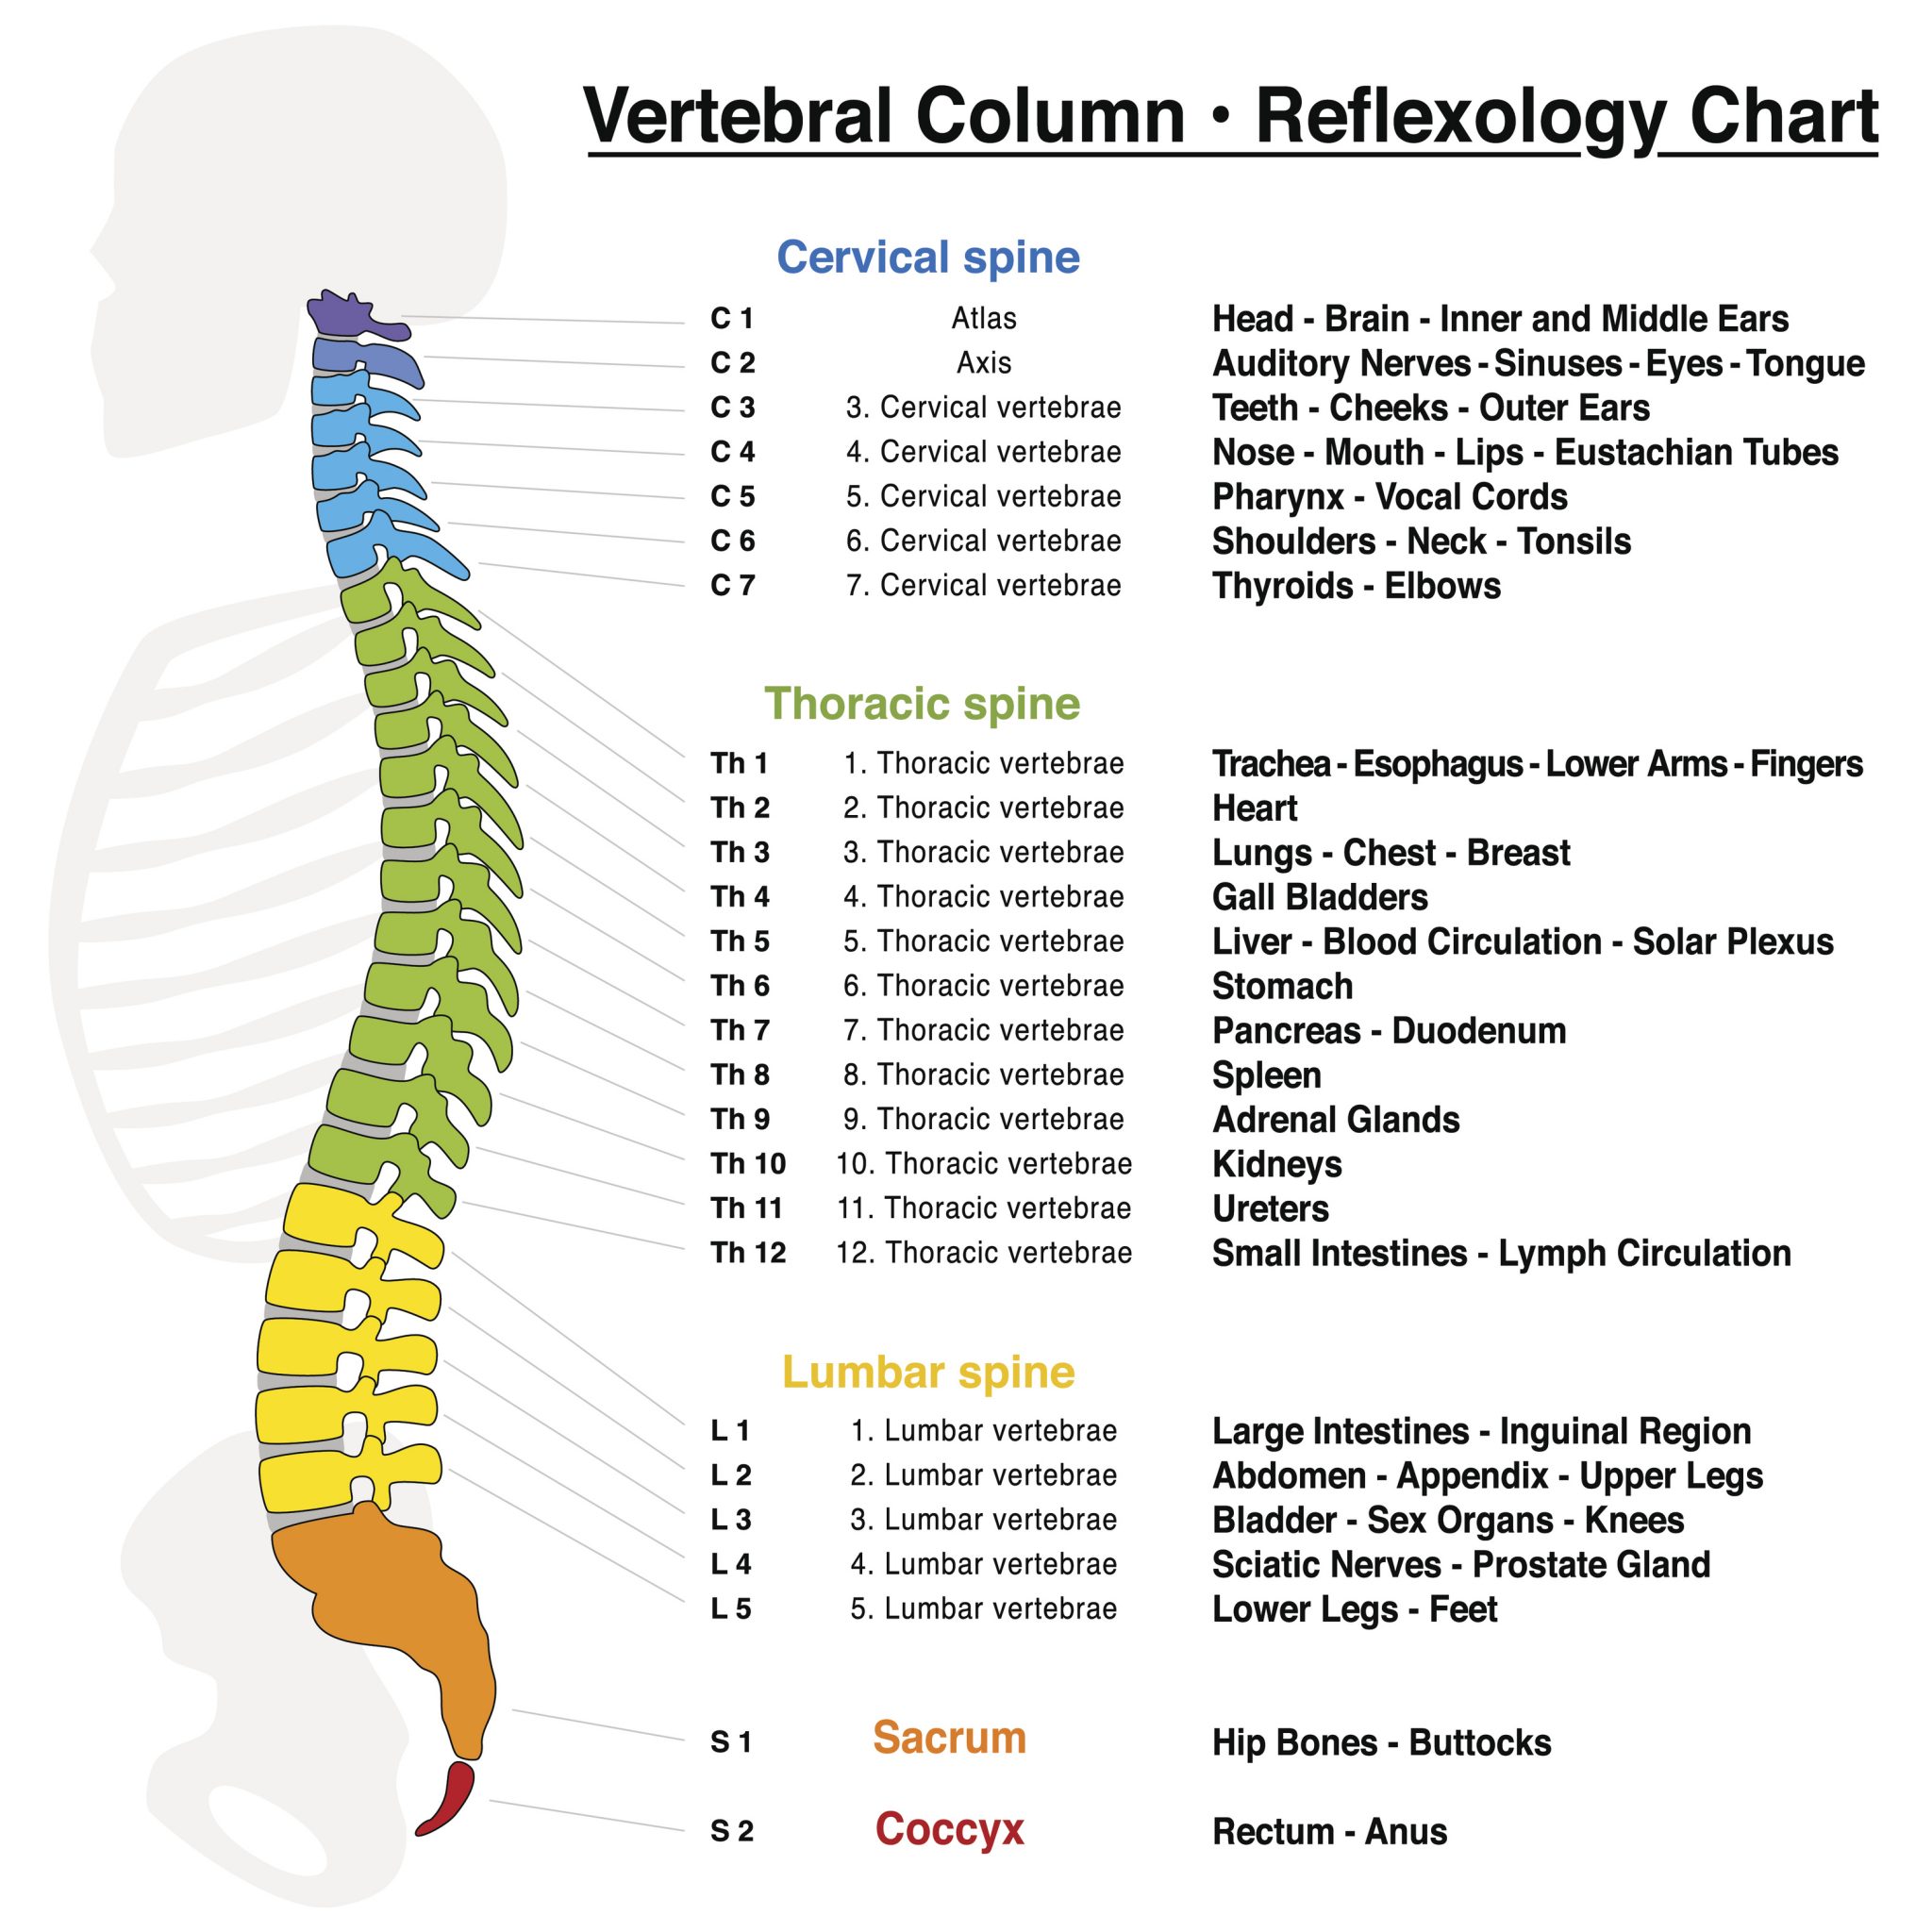

silikonsheet.blogg.se – Spine diagram

diagram of cervical and thoracic spine – Google Search | Spinal cord …

Pin by G Wilk on Anatomy and Physiology | Medical anatomy, Human …

YOUR SPINAL COLUMN – Back To Life Chiropractic

human spine anatomy diagram

Diagram Human Spine Name Description All Sections Vertebrae Vector …

Diagram showing the relationship between spinal nerve roots and …

spine+diagram | SPINAL NERVES & EFFECTS CHART | Nursing | Anatomia y …